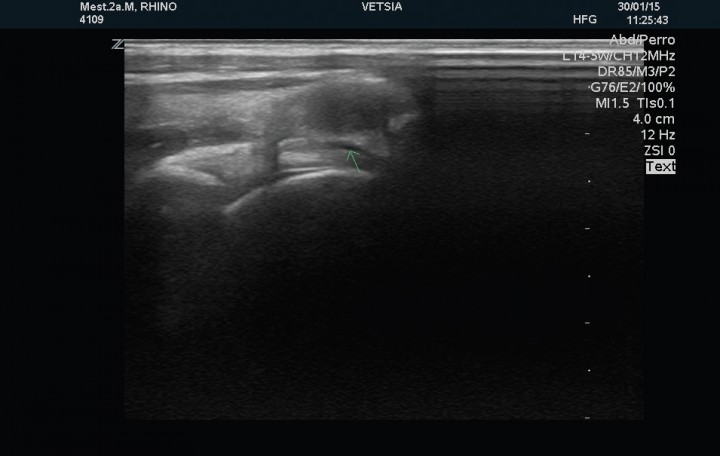

Se realizó examen ecográfico de ambas articulaciones escápulo-humerales con sonda lineal de 12 MHz; los hallazgos ecográficos observados en la articulación izquierda mostraron un tendón del músculo infraespinoso de estructura normal y 2,8 mm de grosor en corte transversal, el tendón del músculo supraespinoso presenta un grosor de 1,7 mm en su porción tendinosa, 4,2 mm en la transición fribrocartilaginosa y de 7,2 mm en la porción fibrocartilaginosa próxima al tubérculo mayor del húmero (zona de máximo grosor), evidenciándose en esta región, próxima a la superficie perióstica, una estructura ecogénica que producía una sombra acústica distal de 3,7mm de diámetro compatible con un foco de mineralización intratendinosa (Fig. 2). El tendón del músculo bíceps braquial presenta su inserción normal en la tuberosidad supraglenoidea con un grosor de 2,7 mm, mostrando su cápsula sinovial un engrosamiento en su porción más proximal (Fig. 3). La cabeza humeral y el cartílago articular se evidencian de contorno liso y grosor normal. La articulación escapulo-humeral derecha no presentaba ningúna alteracion (Fig. 4). La imagen ecográfica es compatible con tendinopatía del tendón del músculo supraespinoso, con mineralización en fibrocartílago de 3,7 mm y signos leves de sinovitis del bicipital.

<p>Corte sagital del tendón del músculo supraespinoso derecho sin alteraciones.</p>

Figura 4

Corte sagital del tendón del músculo supraespinoso derecho sin alteraciones.